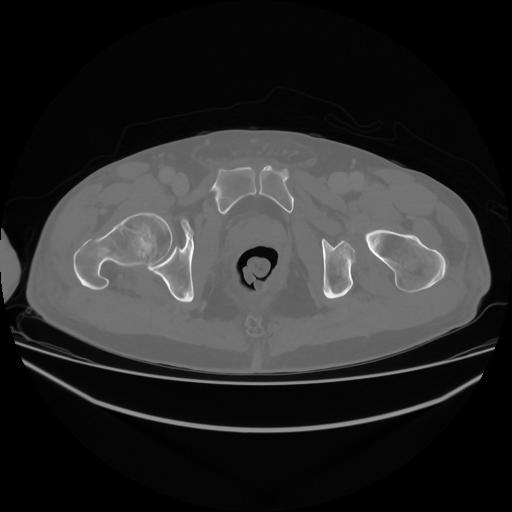

5 CUERPO,CE,Vol,1.0,CUERPO,,